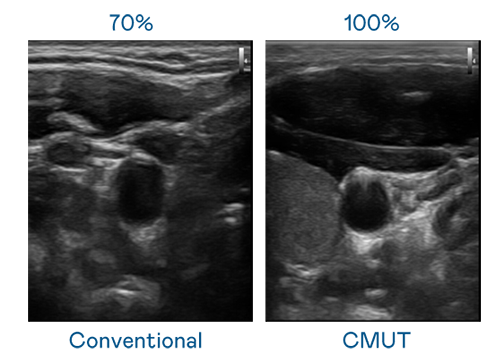

CMUT 技术是一种用电容式微机电元件来产生超音波讯号的技术。与传统 PZT 压电式技术相比,CMUT 频宽增加 30%,更宽频的超音波讯号让影像解析度大幅提升,是实现高影像品质医疗超音波扫描、促进精准医疗发展的关键技术。

大频宽带来超清晰影像

超音波影像的解析度高低,首先取决于探头能发出的讯号频宽。永盈会 CMUT 可提供高清晰的超音波讯号,提供高频宽、高灵敏度、影像纹理细节更高的超音波影像,协助医护人员缩短影像判读时间及利用精准的医疗影像进行诊断。